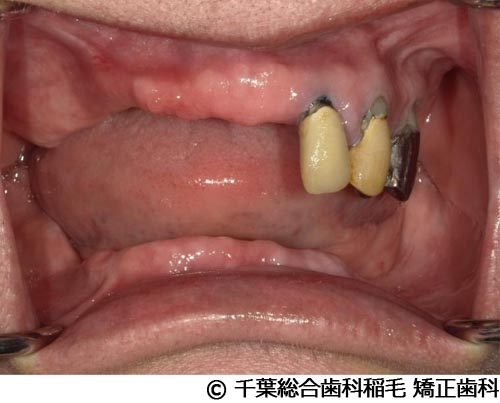

【症例5】All-on-6(オールオン6)

- 治療前

- 治療後

- 治療名

- All-on-6(オールオン6)

- 費用

- 7,500,000円(税込)

- 期間

- 10ヵ月

治療内容

患者様の症状

入れ歯が合わなくなり、お食事も満足にできないとご来院されました。

治療法

ご相談の結果、上顎はインプラントを6本、下顎は7本埋入し、All-on-6(オールオン6)という固定式のインプラント治療を行いました。

治療結果

入れ歯が動いてしまう煩わしさがなくなり、よく噛めるようになったと仰っています。

※治療結果は患者様によって個人差があります。